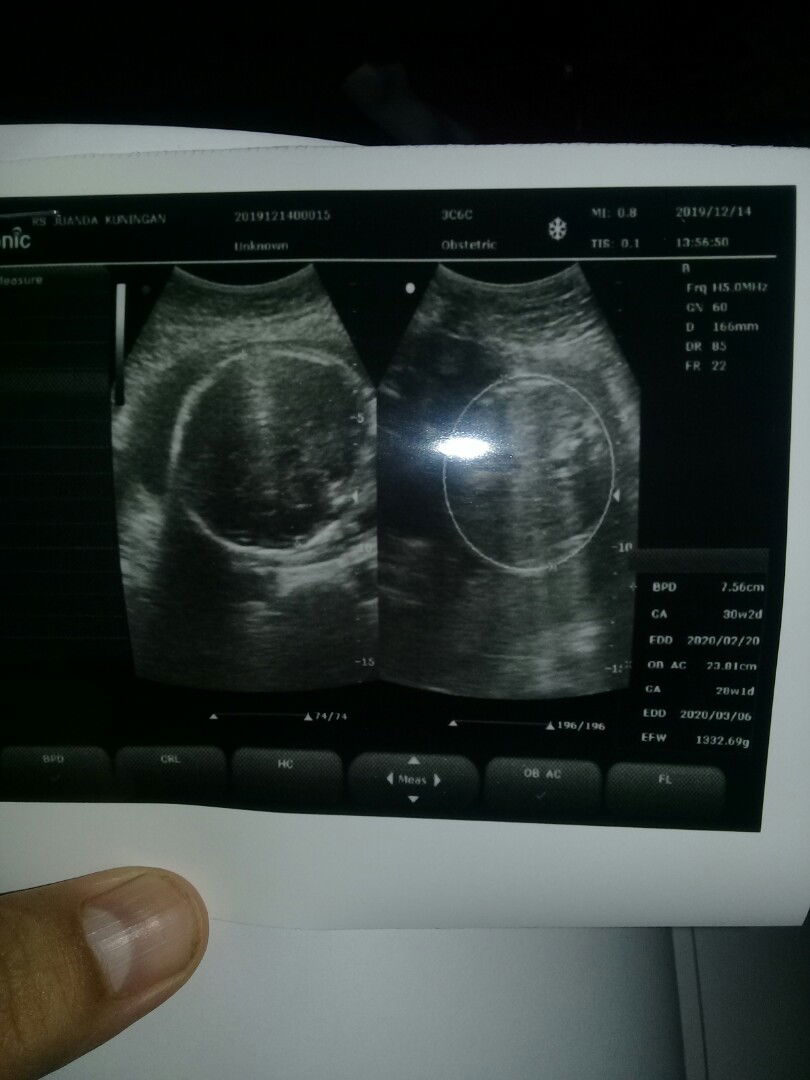

Tlat post .smoga bner ya allohh my beby boy ku ??? 31 week alhmdllah